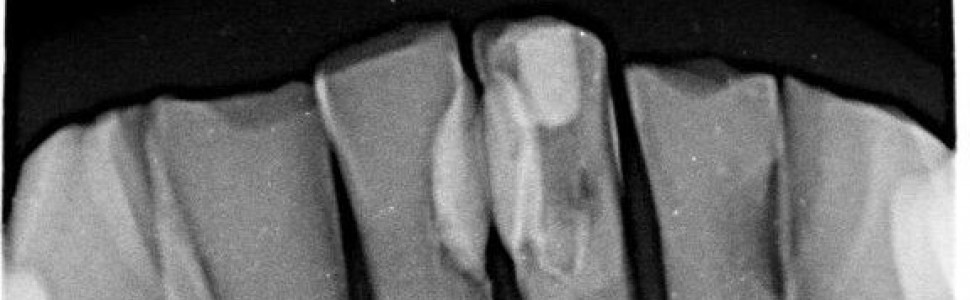

Obliteracja jamy zęba – etiologia, diagnostyka oraz metody postępowania klinicznego

Obliteracja jamy zęba jest procesem prowadzącym do zmniejszenia przestrzeni endodontycznej w wyniku odkładania się związków mineralnych w komorze lub wzdłuż ścian kanału korzeniowego. Do czynników etiologicznych zaliczamy m.in.: urazy, parafunkcje, ubytki próchnicowe, przeprowadzone zabiegi lecznicze przy użyciu środków odontotropowych. Kalcyfikacja najczęściej przebiega bezobjawowo, a jedynym objawem, na który zwraca uwagę pacjent, jest przebarwienie korony zęba. Na podstawie przeglądu piśmiennictwa w pracy przedstawiono etiologię, rodzaje, umiejscowienie i diagnostykę obliteracji oraz metody postępowania klinicznego podczas leczenia kanałowego zębów z kalcyfikacją jamy zęba.

Pulp canal obliteration, caused by the deposition of mineral compounds in the chamber or along the walls of the root canal, results in the reduction of endodontic space. The etiological factors include injuries, para-punctures, carious lesions, and treatment procedures performed with the use of odontotropic agents. Calcification is usually asymptomatic, and the only symptom that the patient notices is discoloration of the tooth crown. Aim of the study: Based on a literature review, the study presents the etiology, types, location and diagnosis of obliteration, and the methods of clinical management during root canal treatment with calcification of the tooth cavity.